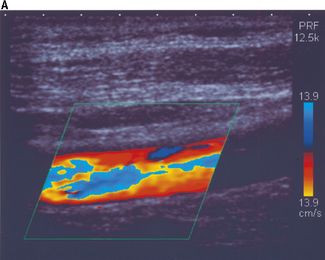

Figure 11.15a illustrates color aliasing which is caused when the color scale is set too low. The Doppler signals are undersampled at a PRF = 12.5 kHz which corresponds to a maximum color scale velocity of 13.9 cm/s. In this example, color flow changes from BLUE to RED are observed within the vessel. Increasing the color scale increases the PRF, from 12.5 kHz to 14 kHz, which is sufficient enough to eliminate aliasing within the image, as demonstrated in Figure 11.15b.

image image

Fig. 11.15 a) The color scale is set too low, resulting in aliasing of the color Doppler signal. The Doppler signals are undersampled at a PRF = 12.5 kHz. b) The color scale and PRF are increased to ensure that the Doppler signals are adequately sampled, resulting in the elimination of aliasing. This is achieved at a higher PRF of 14 kHz